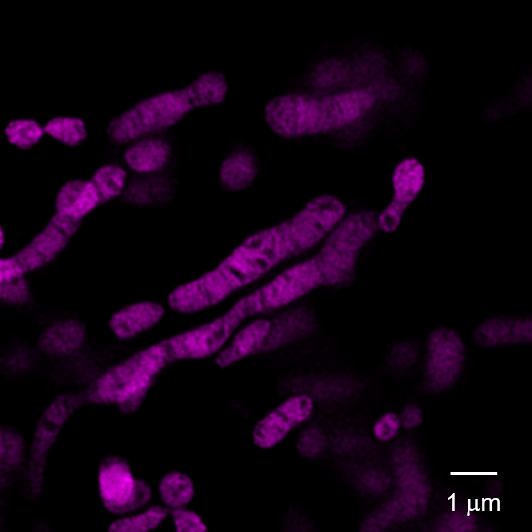

あなたの心、体、魂を変えていくでしょう。Mitofusin-2 Regulates Platelet Mitochondria and Function。神秘に満ちた土地の秘密を発見してください。【全未使用 全極美品】週刊少年ジャンプ展 オールスターカードコレクション コンプ JUMP allstar complete VOL1・2 ドラゴンボール 遊戯王。大貝獣物語 ザ・ミラクル オブ ザ・ゾーン グリフワール編 ストラクチャーBOX◆新品Ss。